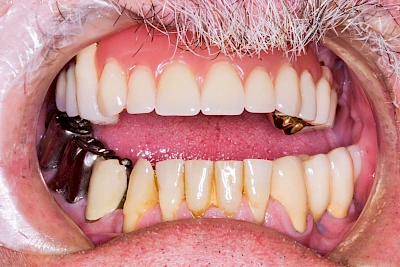

Gehen die Zähne verloren, baut häufig auch der Kieferknochen ab (Knochenschwund). Die Geschwindigkeit und das Ausmaß des Knochenschwundes ist von vielen Faktoren abhängig. Neben der genetischen Veranlagung spielen auch Überbelastungen in Folge, z. B. bei ständigem Knirschen oder Pressen, eine Rolle. Auch wenn Zahnprothesen Tag und Nacht getragen werden, kann die ständige Belastung der Schleimhäute und des Knochens den Knochenschwund beschleunigen.

Aber Achtung: Manche Menschen fühlen sich ohne Zahnprothesen unwohl. Zudem kann es passieren, dass Zahnprothesen (wenn noch eigene Zähne vorhanden sind) nicht mehr passen. Dies gilt vor allem dann, wenn diese Zahnprothesen nicht nur über Nacht, sondern für einen längeren Zeitraum nicht mehr getragen werden.